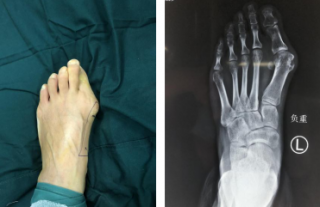

踇外翻俗称“大脚骨”,是一种常见的踇趾向足的外侧过度倾斜、第一跖骨内收的前足畸形,女性居多。

如何治疗踇外翻?

第三代微创踇外翻矫正手术

sararz足踝团队采用4毫米低频超声骨刀微创截骨,切口很小无需缝合;低频超声骨刀锋利、精准、自带注水降温,能更好地保护骨骼血运,使得截骨处更快愈合,手术基本无血渗出,完美修整踇外翻,术后第二天就能下地行走。